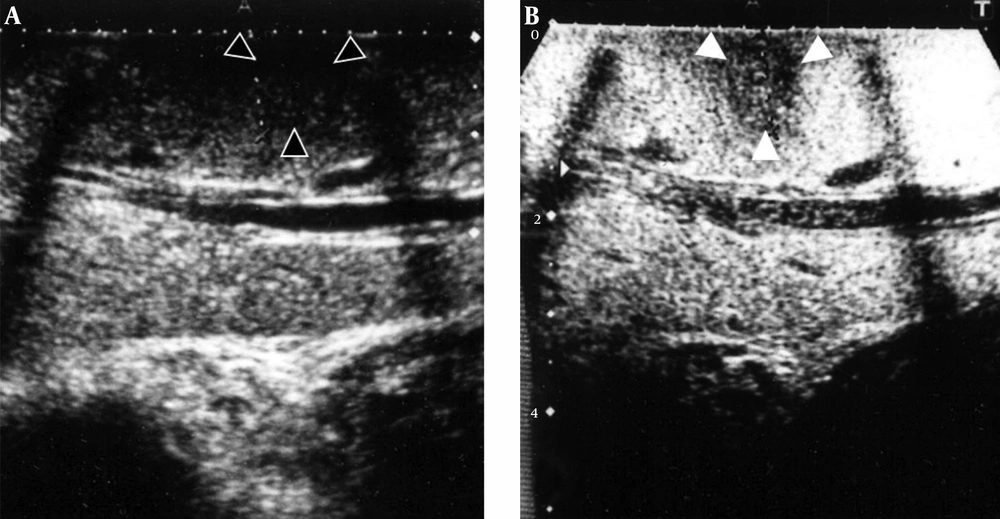

Ultrasonography showed a 17-mm isoechoic tumor that was surrounded by a low-echoic area in the liver metastasis at the first operation. The pseudotumor of SOS was unclear on conventional ultrasonography (Figure 1A), whereas Sonazoid contrast-enhanced ultrasonography in the Kupffer phase visualized a 13-mm low-echoic mass (Figure 1B). Enhanced CT at the early phase showed a ring-enhanced tumor in segment 7 (Figure 2A), whereas the metachronous pseudotumor presented as an unclear hypodense mass without surrounding enhancement (Figure 2B).